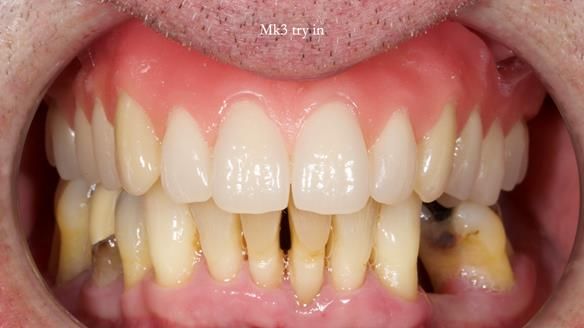

Twelve months after the final extractions, I made the Mk3 definitive complete upper denture.

At Jeremy’s final review:

- Retention, stability and support were excellent.

- Speech was good but not perfect.

- Aesthetics were excellent and Jeremy was very happy with this apspect.

- Sibilance with S’s was still a bit of a problem for him, however, Claire (my nurse) and I could not hear problems with the speech.

- Biting and chewing were no problem at all.